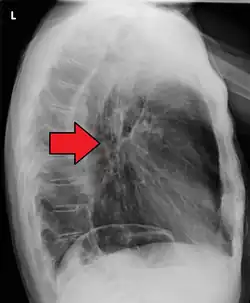

Additional testing is needed to assess how much the cancer has spread (see § Staging, below). Computed tomography (CT) of the chest, abdomen and pelvis can evaluate whether the cancer has spread to adjacent tissues or distant organs (especially liver and lymph nodes). The sensitivity of a CT scan is limited by its ability to detect masses (e.g. enlarged lymph nodes or involved organs) generally larger than 1 cm.[44][45] Positron emission tomography is also used to estimate the extent of the disease and is regarded as more precise than CT alone.[46] PET/MR as a novel modality has shown promising results in preoperative staging with fair feasibility and good correlation in comparison to PET/CT. It can enhance tissue differentiation with lowering the radiation dose to the patient.[47] Esophageal endoscopic ultrasound can provide staging information regarding the level of tumor invasion, and possible spread to regional lymph nodes.

Contrast CT scan showing an esophageal tumor (axial view)

Contrast CT scan showing an esophageal tumor (coronal view)